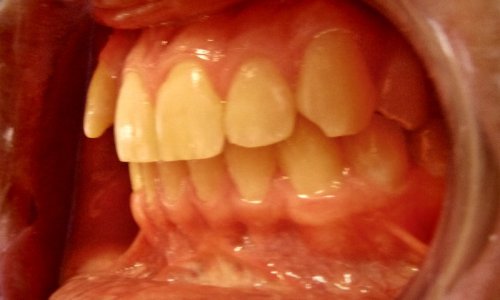

Zgryz Przed

Wada Zgryzu

Stan wyjściowy: Pacjent zgłosił się z problemami estetycznymi i czynnościowymi zgryzu.